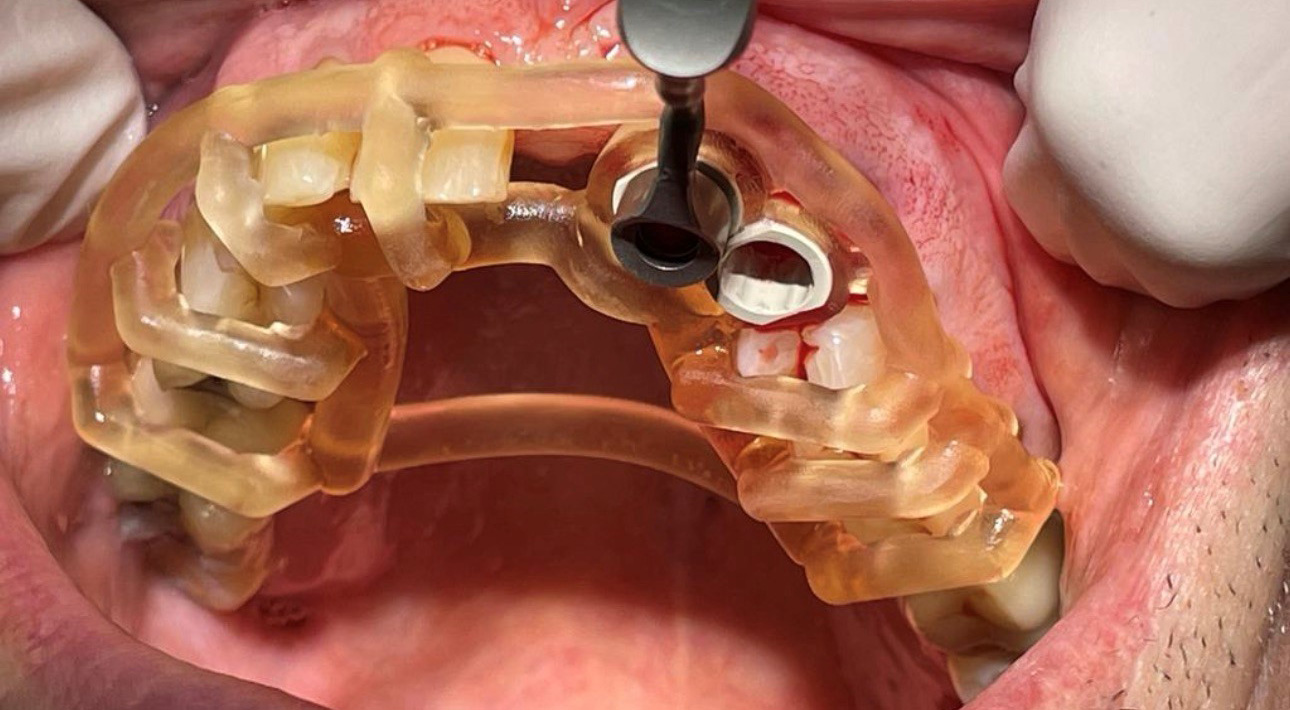

Guided Dental Implants